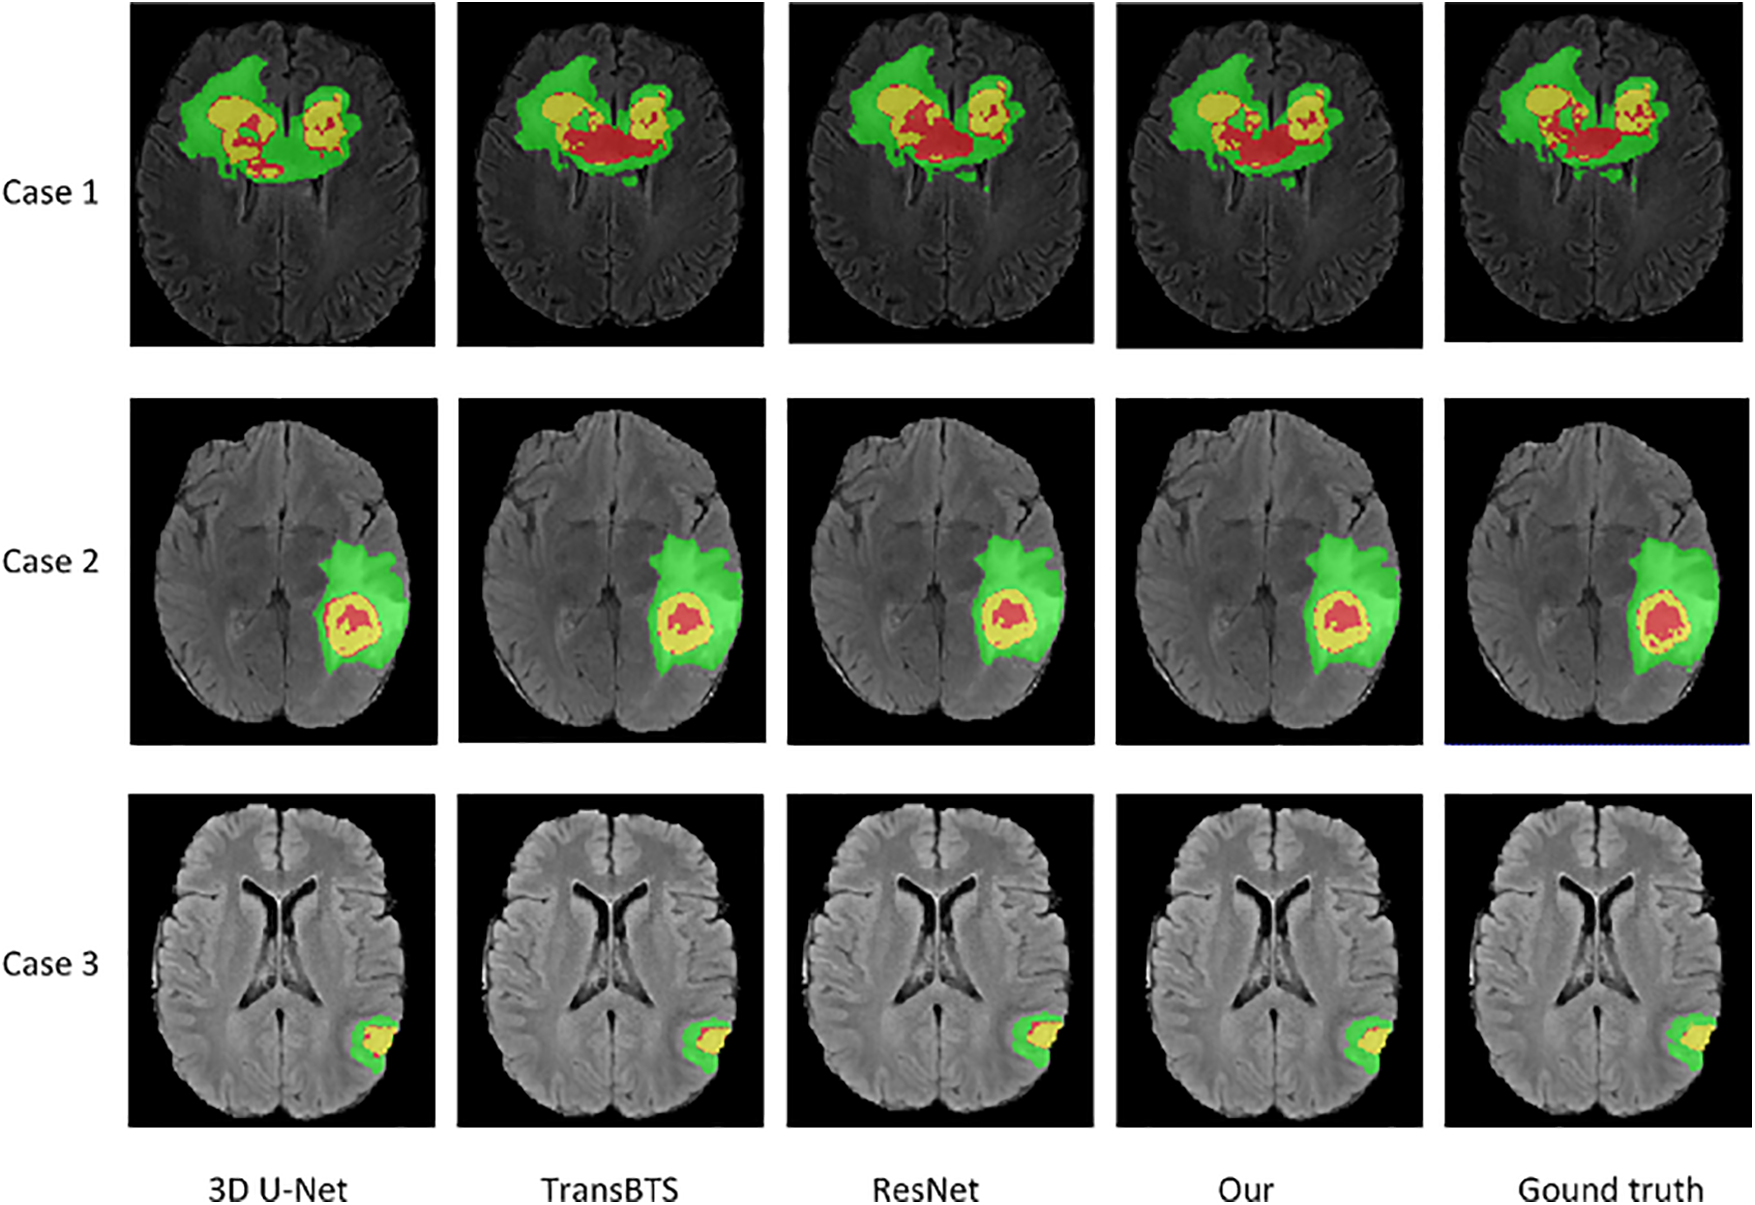

Visual comparison. Fig. 3 visually compares the segmentation results of brain tumors from three cases (from top to bottom: BraTS20_Training_095, BraTS20_Training_170, and BraTS20_Training_233) when using our network and three advanced networks. The segmentation results of three cases show that the 3D U-Net can roughly segment contours of WT and TC regions loosely, but there is misclassification for small region ET. The segmented tumor regions, especially the red ET regions using our method, are closer to the ground truth. In the ground truth tumor regions of case 3, there are very few pixels in the ET region. Our model has the most accurate predictions compared to the other three models, as it can generate feature maps with low-level, mid-level, and high-level information before prediction. Hence, our method accurately predicts the location and classification of tumors, especially small region tumors. In addition, the combo loss function penalizes false positive samples in small regions, improving small tumor region segmentation performance.

Figure 3: Visualization of segmentation results of brain tumors by our network and three advanced networks. Green, yellow, and red indicate edema, enhancing tumor core, necrotic, and non-enhancing tumor core regions